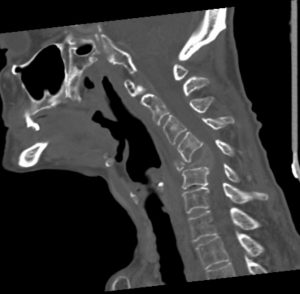

Πρόσθια – Οπίσθια (360ο) Σπονδυλοδεσία Αυχενικής Μοίρας Σπονδυλικής Στήλης